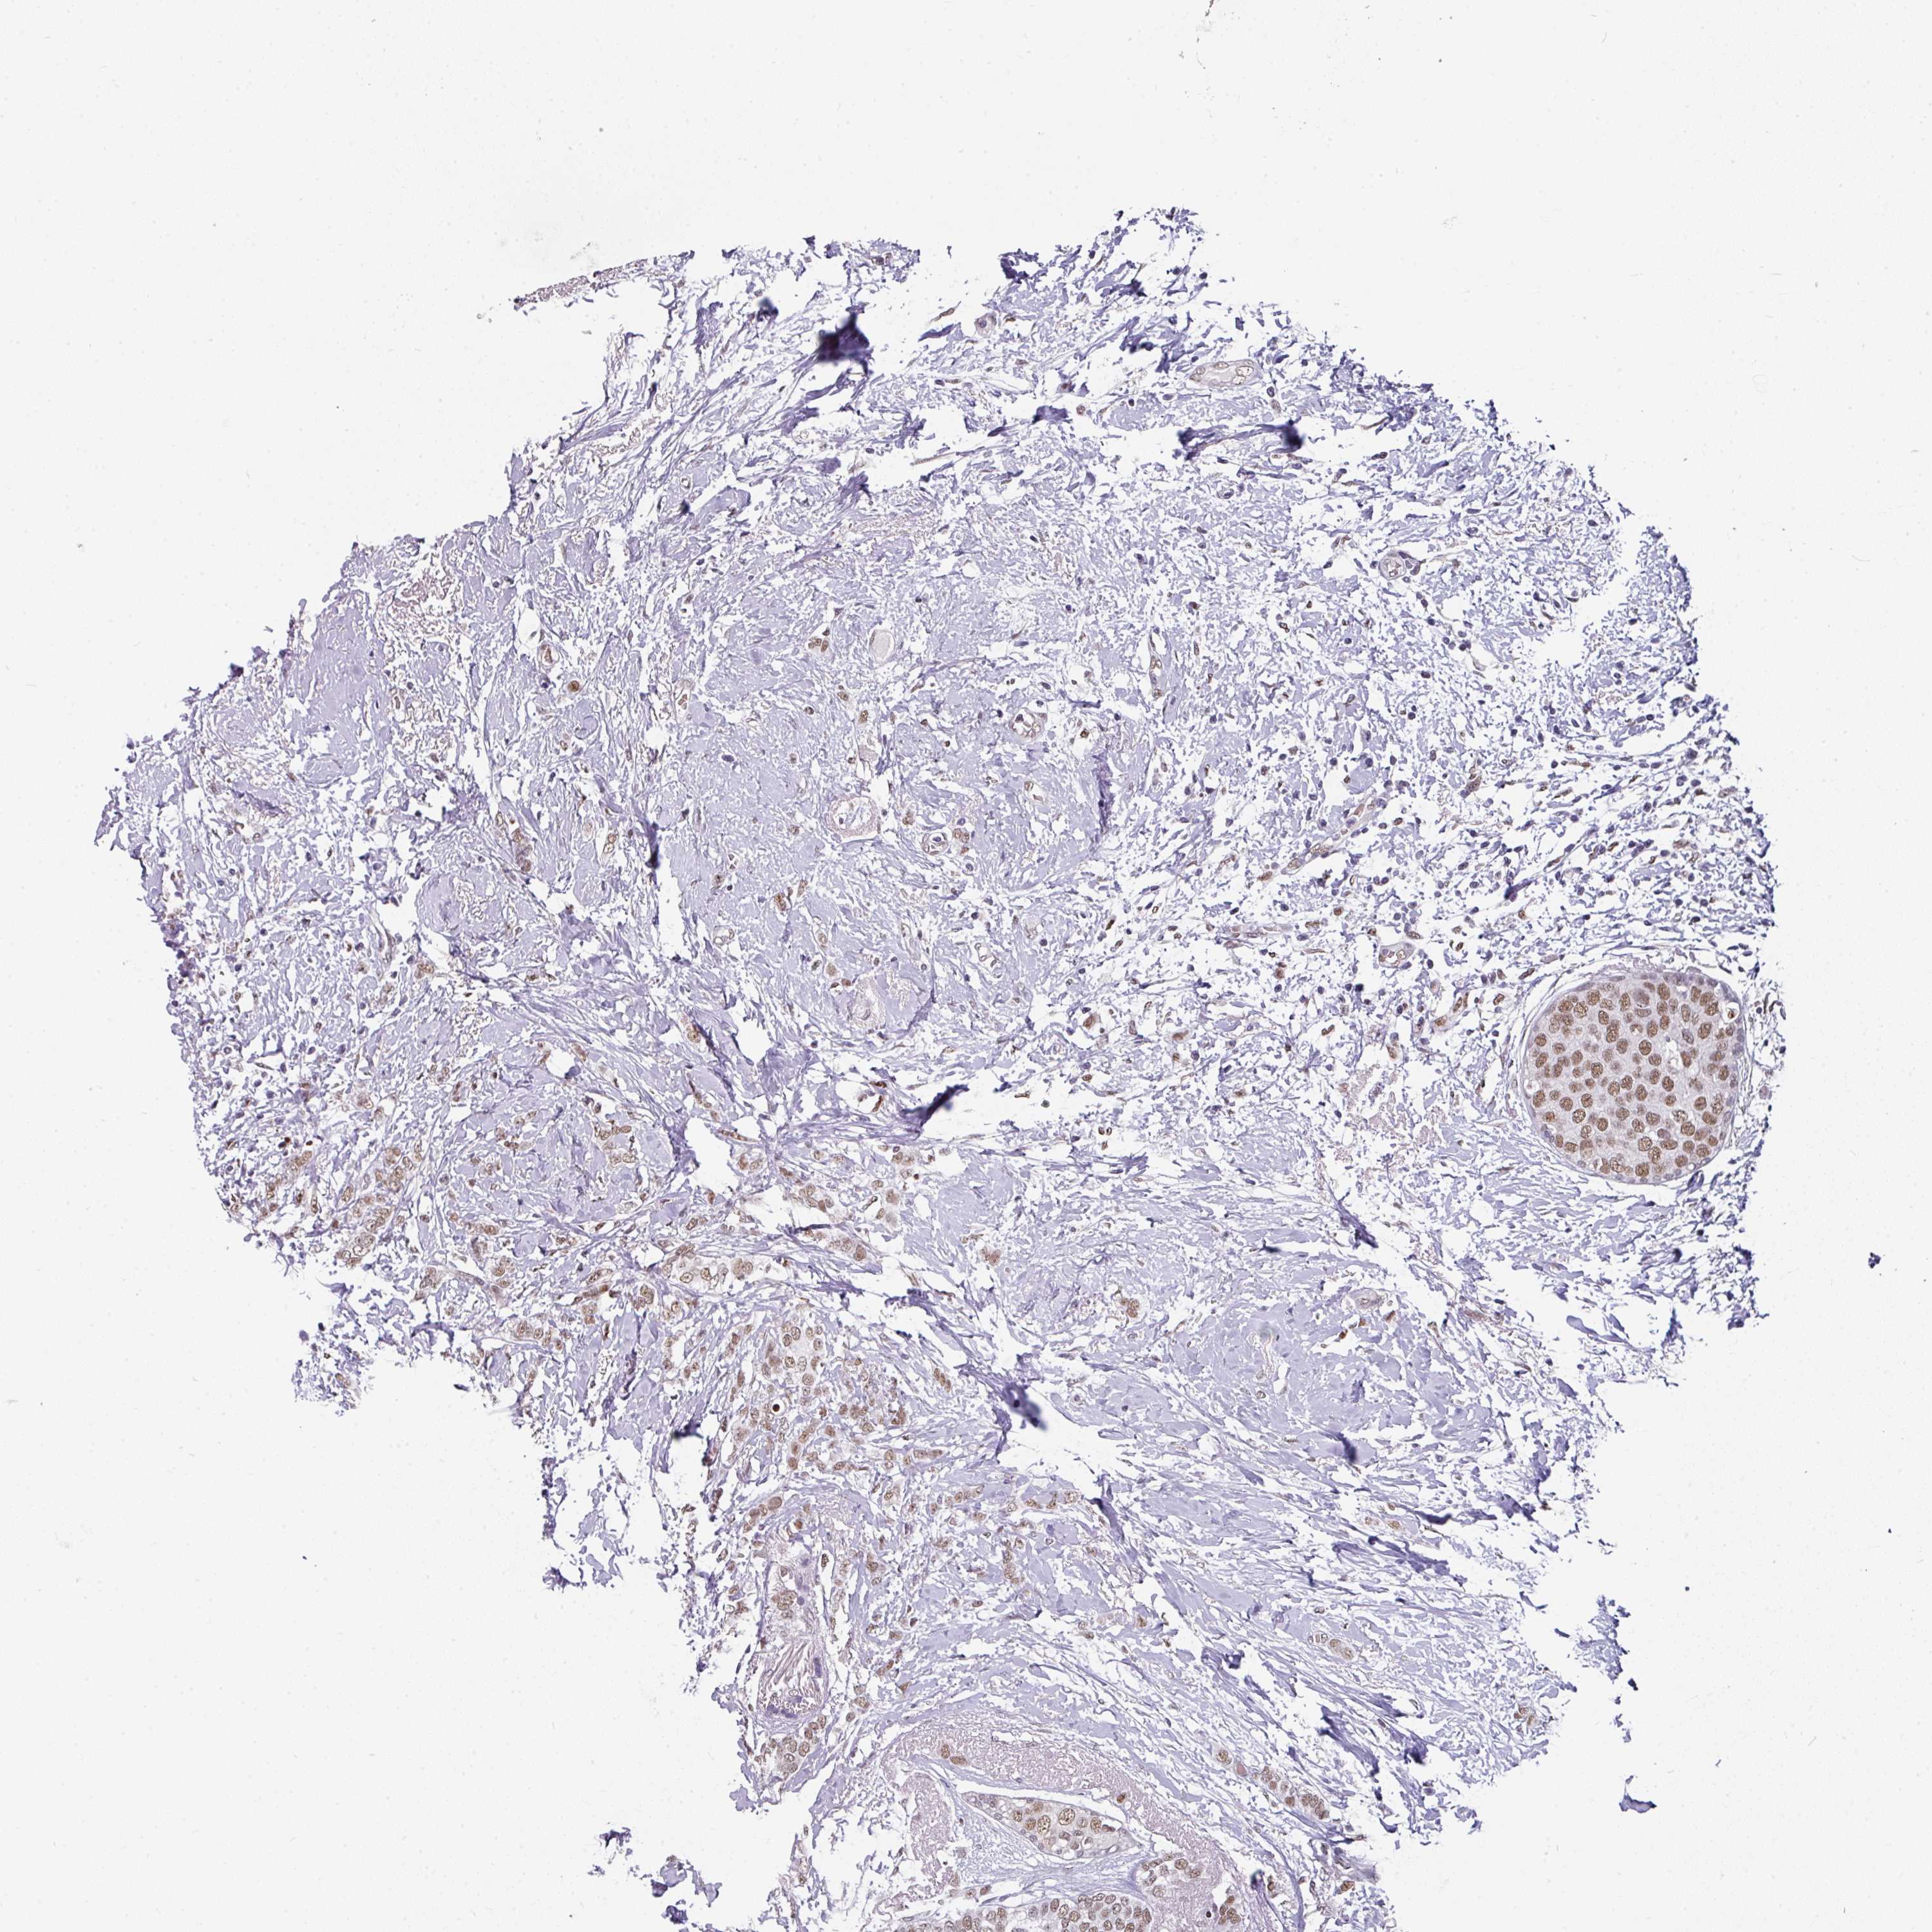

BRCA TCGA BRCA VALIDATION PROTEIN EXPRESSION

Breast cancer

Human cancer